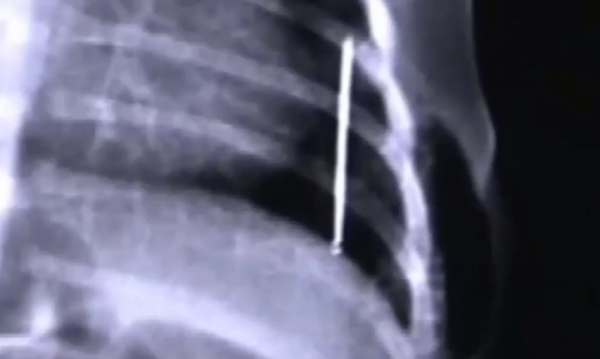

但是做完之後,結果令所有人都大吃一驚,只見醫生看到x光片之後,

發現在孩子的肚子下方,有著一個細長的尖銳物品,仔細一看,發現原來是一顆釘子,

醫生也瞪大了眼睛看了看x光片,發現雨婷的身體裡面又多了兩顆釘子,

而且這次的兩顆釘子存在的位置還不一樣,大小也比之前的要大一點,

醫生為了能夠更精確地確認釘子的位置,就給孩子又拍了一個片子,結果又讓在座各位的心提了起來,

只見這次拍完片子之後,發現雨婷體內的釘子又多了一個,

變成了三個,而且有一根最長的釘子還是橫著放的,這釘子難道還會繁殖不成?